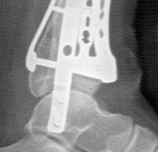

Fig 2.2-6a–b Immediate postoperative x-rays showing restoration of the ankle mortise and distal tibia alignment through anatomical and stable fracture fixation.

1. AP view.

2. Lateral view.